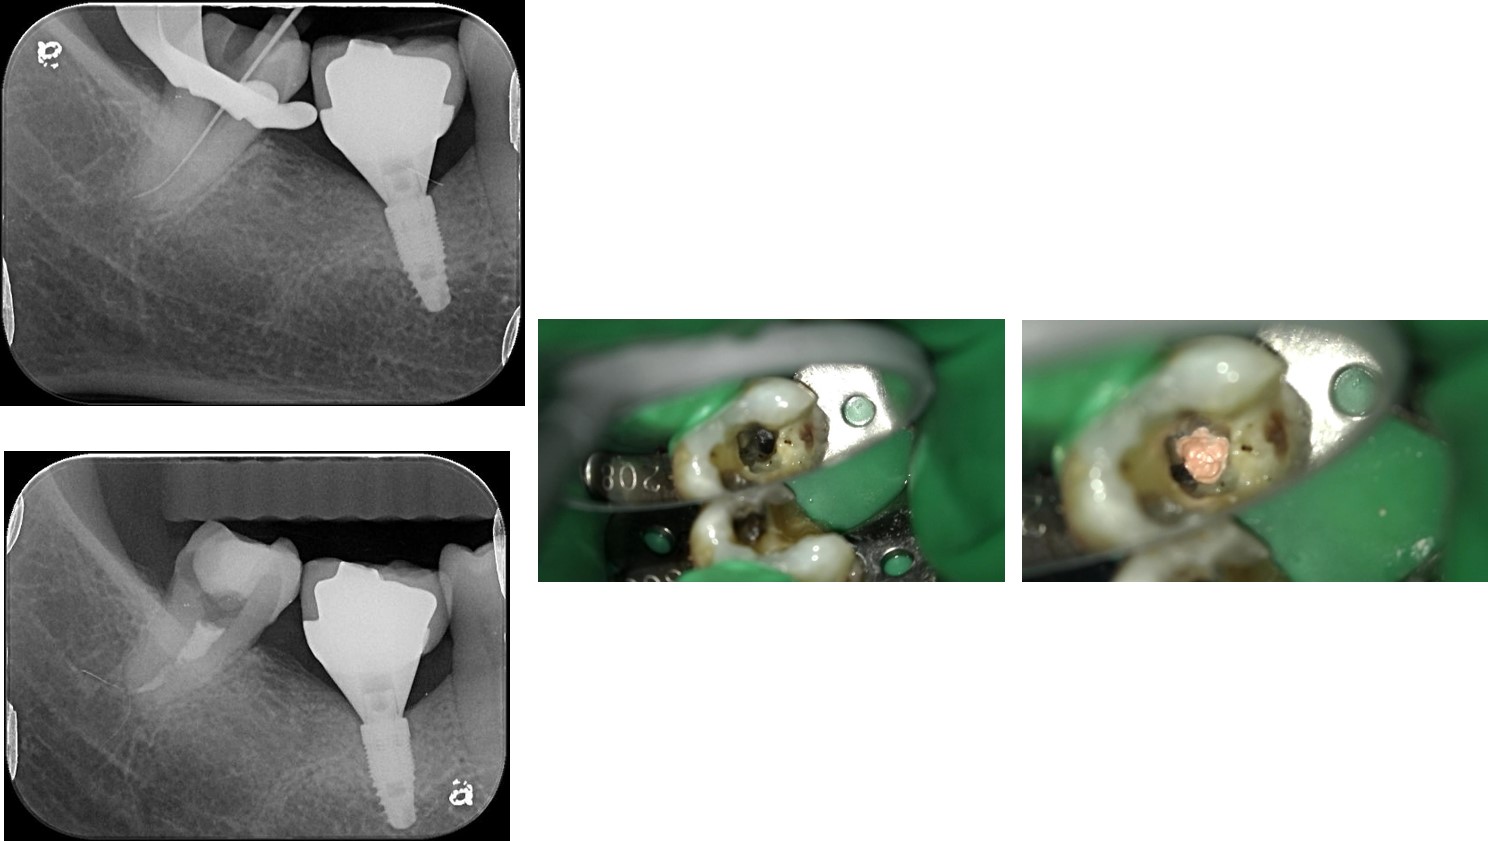

顯微根管治療

鑄造金屬釘柱

水雷射牙冠增長手術

膺復前評估牙齦、牙齒狀態